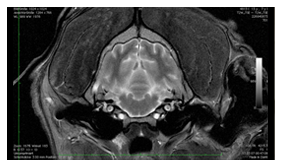

Die Abklärung neurologischer Patienten mittels Computer- und Kernspintomographie (CT- und MRT-Diagnostik) erlaubt die exakte Beurteilung von Rückenmark- und Bandscheibenveränderungen und stellt für unsere Chirurgen die Grundlage neurochirurgischer Eingriffe an der Wirbelsäule dar.